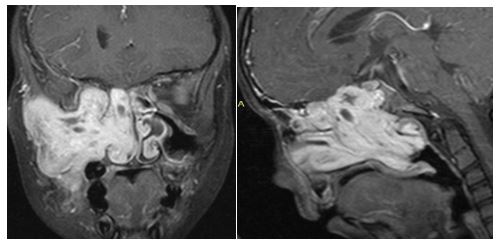

3. 10/2017. Masculino 17 años con obstrucción nasal de inicio gradual, epistaxis recurrente derecha, masa la cavidad nasal bilateral y abombamiento de paladar blando de 4 años de evolución. TC y RM con extensión a naso y orofaringe con extensión a seno maxilar, fosa pterigomaxilar, infratemporal derecha y extensión intracraneal mínima. Clasificación IIIA (Radkowski) IV (Chandler). Se realiza angiografía, embolización de ramas de carótida externa bilateral, y resección vía endoscópica, transpalatina y Degloving, resección de 95% de tumor con tumor residual en fosa infratemporal, posterior radioterapia, con reducción gradual de tumor en los últimos 8 meses.

3

4. 03/2018. Masculino 16 años con obstrucción nasal de inicio gradual, epistaxis recurrente izquierda, masa la cavidad nasal bilateral y abombamiento de paladar blando de 3 años de evolución. TC y RM con extensión a seno maxilar izquierdo fosa infratemporal, fisura infraorbitaria e intracraneal izquierdo. Clasificación IIIA (Radkowski) IV (Chandler). Se realiza angiografía, embolización y resección vía Degloving, con resección completa de tumor, buena evolución posquirúrgica a 6 meses, sin recurrencia.

4